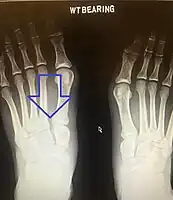

Lisfranc dislocation of the left foot due to lisfranc ligament rupture as seen on bilateral weight bearing radiographs.[1]

In a high energy injury to the midfoot, such as a fall from a height or a motor vehicle accident, the diagnosis of a Lisfranc injury should, in theory at least, pose less of a challenge. There will be deformity of the midfoot and X-ray abnormalities should be obvious. Further, the nature of the injury will create heightened clinical suspicion and there may even be disruption of the overlying skin and compromise of the blood supply. Typical X-ray findings would include a gap between the base of the first and second toes.[10] The diagnosis becomes more challenging in the case of low energy incidents, such as might occur with a twisting injury on the racquetball court, or when an American Football lineman is forced back upon a foot that is already in a fully plantar flexed position. Then, there may only be complaint of inability to bear weight and some mild swelling of the forefoot or midfoot. Bruising of the arch has been described as diagnostic in these circumstances but may well be absent.[11] Typically, conventional radiography of the foot is utilized with standard non-weight bearing views, supplemented by weight bearing views which may demonstrate widening of the interval between the first and second toes, if the initial views fail to show abnormality. Unfortunately, radiographs in such circumstances have a sensitivity of 50% when non-weight bearing and 85% when weight bearing, meaning that they will appear normal in 15% of cases where a Lisfranc injury actually exists.[12] In the case of apparently normal x-rays, if clinical suspicion remains, advanced imaging such as magnetic resonance imaging (MRI) or computed tomography (CT scan) is a logical next step.[13]